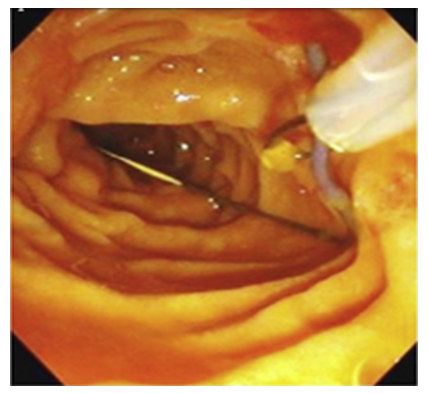

During the second stage of surgery (Rendezvous), joint work of surgical and endoscopic teams is necessary. The surgeon performed an incision of the cystic duct just below the previously applied clip and inserted a 0.035 Fr endoscopic string 450 cm long into the cystic duct through a 3 mm diameter trocar. Then he conducted it antegradely through the LDP into the lumen of the duodenum. After the string was passed through the LDP, the endoscopist conducted a video duodenoscope in the duodenum in the usual way and visualized the LDP in the lumen of which the string was located. From the side of the lumen of the duodenum, the string was captured with a modified hollow endoscopic bougie (Fig. 3).At the third endoscopic stage of the hybrid surgical intervention, the papillot was lowered along the string and inserted into an ampoule of LDP, thus performing selective intubation of the choledochus. Retrograde endoscopic papillosphincterotomy (EPST) was performed using the standard method (Fig. 4).Then the papilloma was removed, leaving an endoscopic string in the biliary tract. Depending on the diameter of the common bile duct and the size of the stones, lithoextraction was performed with four-string Dormia baskets of various sizes and stiffness (Fig. 5).  | Figure 3. Capturing the string in the lumen of the duodenum |

| Figure 4. Papillosphincterotomy |